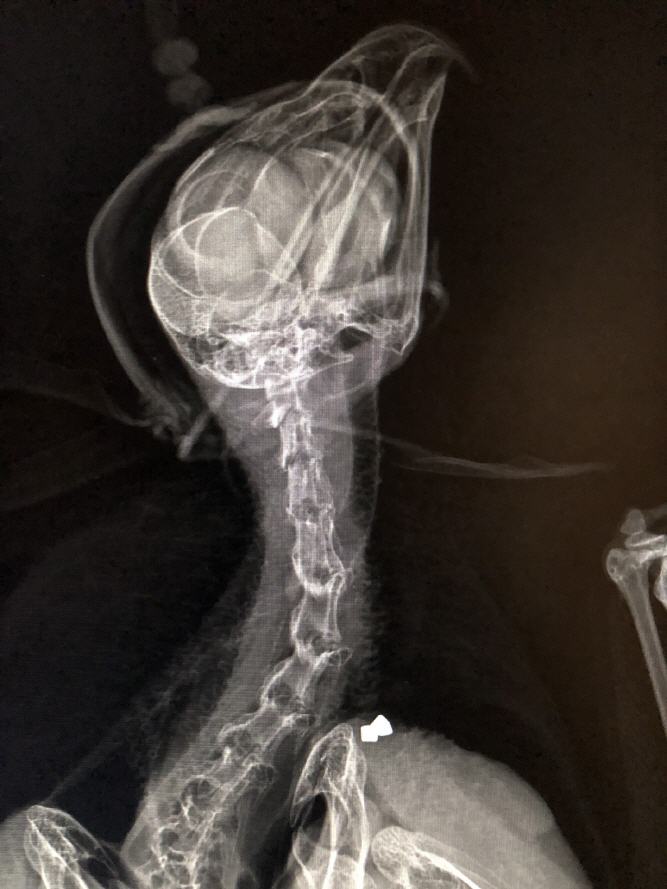

Patientengalerie

Wundversorgung bei einem Steinadler